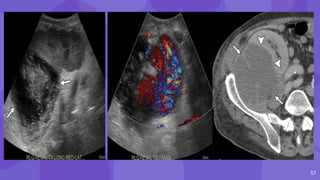

Post Biopsy Renal AVF and Pseudoaneurysm

● AVF may form when an artery and vein are

lacerated, whereas PA results when only the

artery is lacerated

● AVF Pseudoaneurysm

AVFs have a feeding

artery with a high-

velocity low-resistance

waveform at spectral

analysis

● narrow neck

● to-and-fro pattern of

blood flow

● yin-yang sign

15

Bidirectional flow

Renal artery

Early draining

vein

pseudoaneurysm

16

early draining vein

from the AVF

14 Post Biopsy RenalAVF and Pseudoaneurysm ● AVF may form when an artery and vein are lacerated, whereas PA results when only the artery is lacerated ● AVF Pseudoaneurysm AVFs have a feeding artery with a high- velocity low-resistance waveform at spectral analysis ● narrow neck ● to-and-fro pattern of blood flow ● yin-yang sign

15 Bidirectional flow Renal artery Earlydraining vein pseudoaneurysm

• #15 AVF may form when an artery and vein are lacerated, whereas PA results when only the artery is lacerated. It is important to distinguish between a small hemodynamically insignificant AVF and a pseudoaneurysm color Doppler both AVFs and pseudoaneurysms can appear as focal areas with disorganized blood flow extending beyond the margins of the normal vessel intrarenal pseudoaneurysm may appear as a mildly complex cystic structure but can also mimic a simple renal cyst. Classic color Doppler findings of postbiopsy pseudoaneurysm, particularly those with a narrow neck, include a to-and-fro pattern of blood flow within the neck and the yin-yang sign of swirling blood within the sac

• #16 Postbiopsy pseudoaneurysm and arteriovenous fistula (AVF) Color Doppler image shows a round area of bidirectional flow (arrow) in the upper transplant kidney, consistent with a pseudoaneurysm. Spectral analysis at a site of focal aliasing near the pseudoaneurysm shows high-velocity systolic flow and low-resistance diastolic flow, characteristic features of an AVF Three-dimensional volume-rendered image shows the renal artery (white arrow) with an early draining vein (black arrow) as well as the pseudoaneurysm (arrowhead).

• #17 Image from subtraction angiography shows the pseudoaneurysm (arrowhead) and the early draining vein from the AVF (arrow) Same AVF treated with coil embolization. postprocedure AVFs have been reported in up to 10% of renal allograft biopsies, most of which are asymptomatic with no clinically significant hemodynamic consequences. These cases can be treated conservatively and can be followed up with US as needed, with 70% regressing or resolving spontaneously. Large or symptomatic AVFs resulting in abnormal large or persistent gross hematuria or significant hypertension occur in only 1%–2% of cases and can be treated with catheter embolization